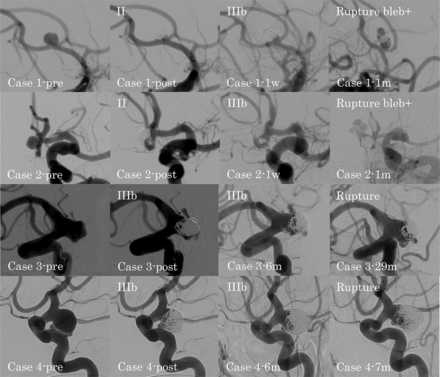

DSA findings for ruptured recanalized aneurysms in the ruptured group. Case 1-pre: preprocedural anterior communicating artery aneurysm; case 1-post: class II aneurysm occlusion immediately after the procedure; case 1–1w: class IIIb recanalization at 1 week after the procedure; case 1–1m: ruptured recanalized aneurysm with a new bleb at 1 month after the procedure; case 2-pre: preprocedural anterior communicating artery aneurysm; case 2-post: class II aneurysm occlusion immediately after the procedure; case 2–1w: class IIIb recanalization at 1 week after the procedure; case 2–1m: ruptured recanalized aneurysm with a new bleb at 1 month after the procedure; case 3-pre: preprocedural ICA–posterior communicating artery aneurysm; case 3-post: class IIIb aneurysm occlusion immediately after the procedure; case 3–6m: progression of the class IIIb recanalization at 6 months after the procedure; case 3–29m: ruptured recanalized aneurysm at 29 months after the procedure; case 4-pre: preprocedural ICA–posterior communicating artery aneurysm; case 4-post: class IIIb aneurysm occlusion immediately after the procedure; case 4–6m: progression of the class IIIb recanalization at 6 months after the procedure; case 4–7m: ruptured recanalized aneurysm at 7 months after the procedure.

In the ruptured group, 4 recanalized aneurysms ruptured. In patients 1 and 2, both with an anterior communicating artery (AcomA) aneurysm, the type of recanalization changed from class II to IIIb, and both aneurysms ruptured with formation of a new bleb at 1 month after coil embolization. In patients 3 and 4, both with an ICA-PcomA aneurysm, the type of recanalization was class IIIb, and the aneurysms ruptured at 29 and 7 months after coil embolization, respectively. All 4 patients with ruptured recanalized aneurysms were receiving continued antiplatelet therapy at the time of rupture. Recanalized aneurysms in the ruptured group tended to rupture earlier than those in the unruptured group.